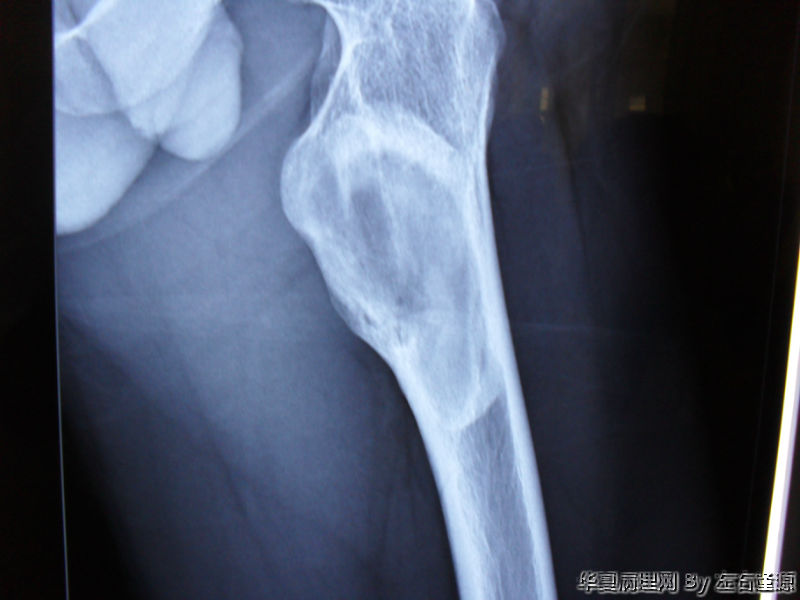

男19岁 左股骨上段异常增殖

• 男19岁 左股骨上段异常增殖图4

图4

周围有骨母细胞,是骨纤维结构不良。

“纤维结构不良”和“骨纤维结构不良”确实不是一个概念,后者骨小梁周围有骨母细胞,并且有特殊的发病部位。本例骨小梁周围大部分没有骨母细胞,是纤维结构不良。,而不是骨纤维结构不良。